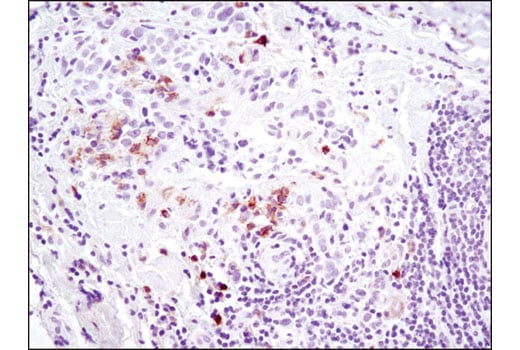

Immunohistochemical analysis of paraffin-embedded breast carcinoma using Axl (C89E7) Rabbit mAb. Note staining of infiltrating cells.

Immunohistochemistry Image 1: Axl (C89E7) Rabbit Monoclonal Antibody